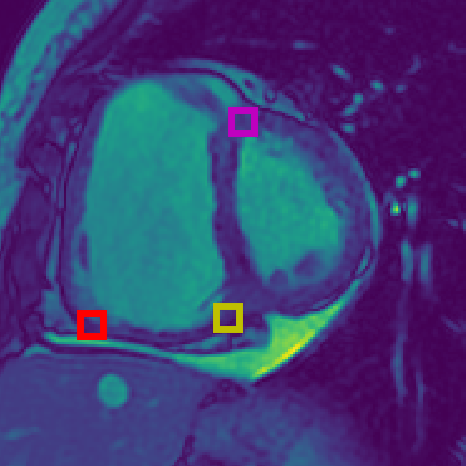

Figure 2: (a) Landmarks for Short Axis (SA) CMR: Magenta = superior right ventricle insertion point valve; Yellow = inferior right ventricle insertion point; Red = inferior lateral reflection of right ventricle free wall. (b) Landmarks for 4 chamber (4CH) CMR: Magenta = tricuspid valve; Yellow = mitral valve; Red = apex of left ventricle. (c) Subset of Landmarks included in the Cephalometric dataset [8]. Displayed landmarks are used in the aleatoric uncertainty analysis (Sec. 6.7).

We perform our experiments using three datasets. The first two datasets are from the ASPIRE Registry [33], containing Cardiac Magnetic Resonance Imaging (CMR) sequences, from a 1.5 Tesla GE HDx (GE Healthcare, Milwaukee, USA) system using an eight-channel cardiac coil. Images were acquired using a cardiac-gated multislice balanced steady-state free precession sequence (20 frames per cardiac cycle, slice thickness 10mm, 0mm inter-slice gap, field of view 480mm, acquisition matrix 256×200256200256\times 200, flip angle 60°60°60\degree, BW 125 KHz/pixel, TR/TE 3.7/1.6 ms). Each subject has a four chamber (4CH) view and/or a short axis view (SA). Each CMR sequence has a spatial resolution of 512×512512512512\times 512 pixels, where each pixel represents 0.9375mm of the organ, and the first frame was used for landmark localization in this study. There are 303 SA images, each with three annotated landmarks: the inferior right ventricle insertion point (infSA), the superior right ventricle insertion point (supSA), and the inferior lateral reflection of the right ventricle free wall (RVSA). There are 422 4CH images, each with three annotated landmarks: the apex of the left ventricle at end diastole (LVDEV Apex), the mitral valve (mitral), and tricuspid valve (tricuspid). The 4CH dataset represents a more challenging landmark localization task as the images have much higher variability than the SA dataset. The landmarks were decided and manually labelled by a radiologist, as shown in Figs. 2(a) & 2(b). For this study, we consider the SA images the EASY dataset, and the 4CH images the HARD dataset.